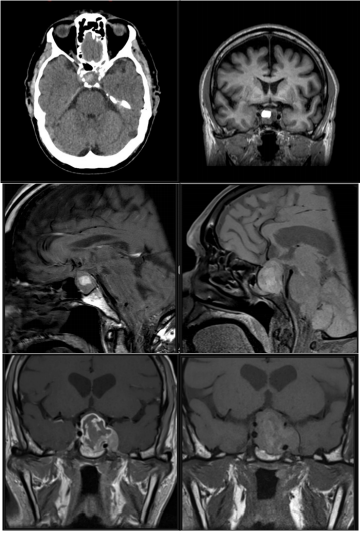

1. Based on the detailed history given by Dr. AlJadir, both CT and MRI images of the pituitary were reviewed.

2. CTHead showed a dense enlarged pituitary gland with a hyperdense area on its right side consistent with hemorrhage…

Imaging

A well-circumscribed mass is present within the expanded sellaturcica. This mass has suprasellar extension and demonstrates iso-intense signal on T1 weighted imaging, heterogeneous but predominantly low signal on T2 weighted imaging, and has predominantly peripheral enhancement, the lesion mildly bulges into the right cavernous sinus with no definite invasion. The optic chiasm is superiorly displaced by the mass and drapes over it. The lesion elevates anterior aspect of floor of the third ventricle without causing hydrocephalus.

CT- head nov. 20

1. The hyper density noted in the Pituitary Gland in the previous studies resolved completely, indicating that there is no fresh hemorrhage …

2. Normal brain parenchyma and ventricular system, normal cerebral sulci and basal cistern…